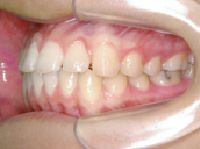

1) 主訴 前歯で咬むことができない

2) 診断名 前歯部開咬

4) 治療に用いた装置 ストレートタイブマルチブラケットシステム(018x025スロット)

パラタルバー、前歯はセラミックブラケット

5) 抜歯 すべての智歯(親知らず)計4本

6) 治療期間 開始時から装置装着まで3か月、マルチブラケット期間1年6か月、保定期間4年